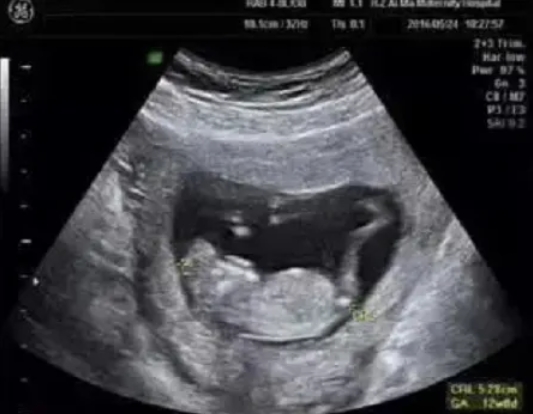

在为孕妈妈们做NT检查的同时,对于胎儿的结构也进行了详细的检查,并且发现了多例胎儿严重结构缺陷。

检查选在孕11~13周+6天进行,相当于头臀长45-84mm时测量,超过84mm检查结果会不准确。

孕早期除了可以确定孕周、诊断死胎、异常妊娠、多胎妊娠,进行胎儿染色体异常的早期筛查与诊断之外,也具备进行严重结构畸形筛查的科学依据。